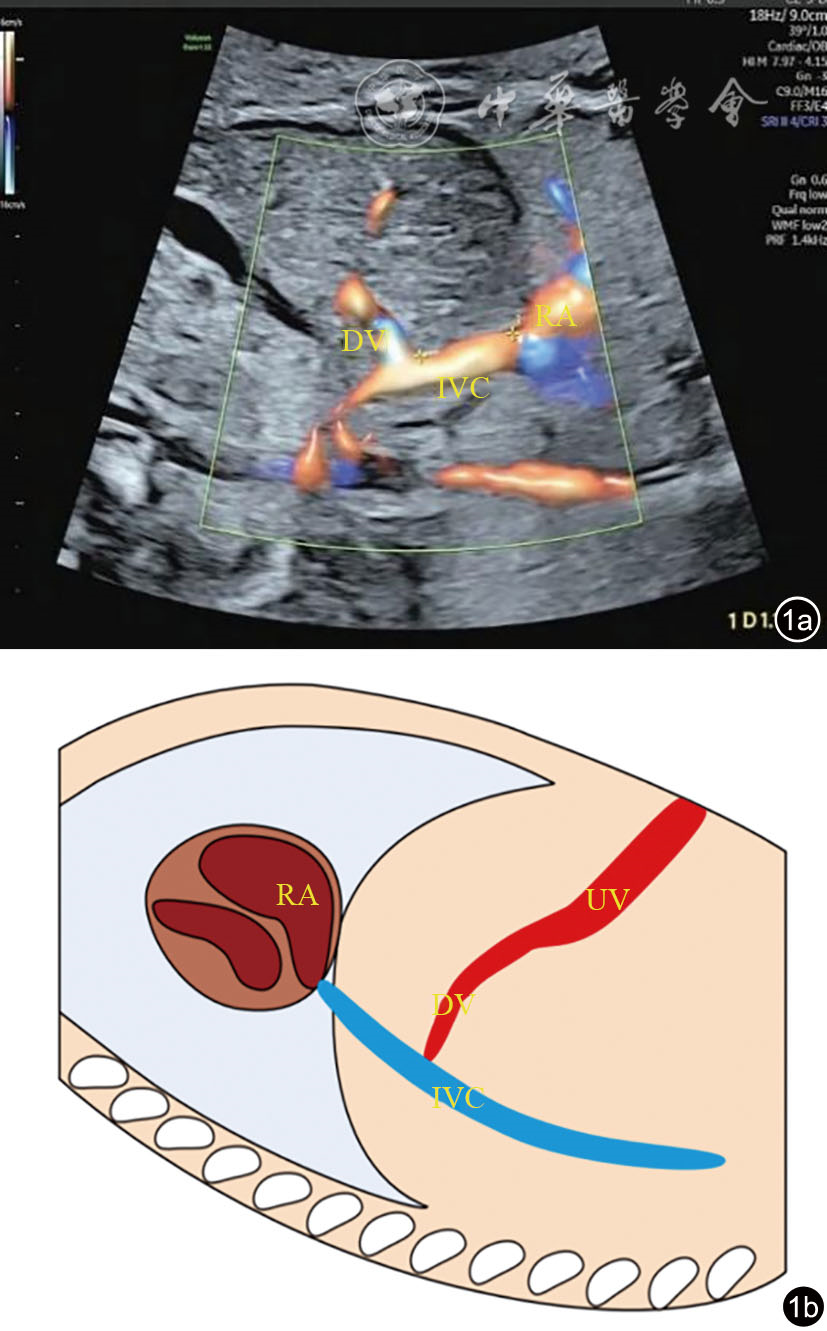

图1 静脉导管异常汇入下腔静脉超声图像及示意图。图a为胎儿静脉导管未进入膈下前庭,在膈前漏斗下方可见一短小静脉导管与腹腔段下腔静脉垂直连接,距右心房开口约1.18 cm;图b为静脉导管异常汇入下腔静脉示意图 注:DV为静脉导管;IVC为下腔静脉;RA为右心房;UV为脐静脉